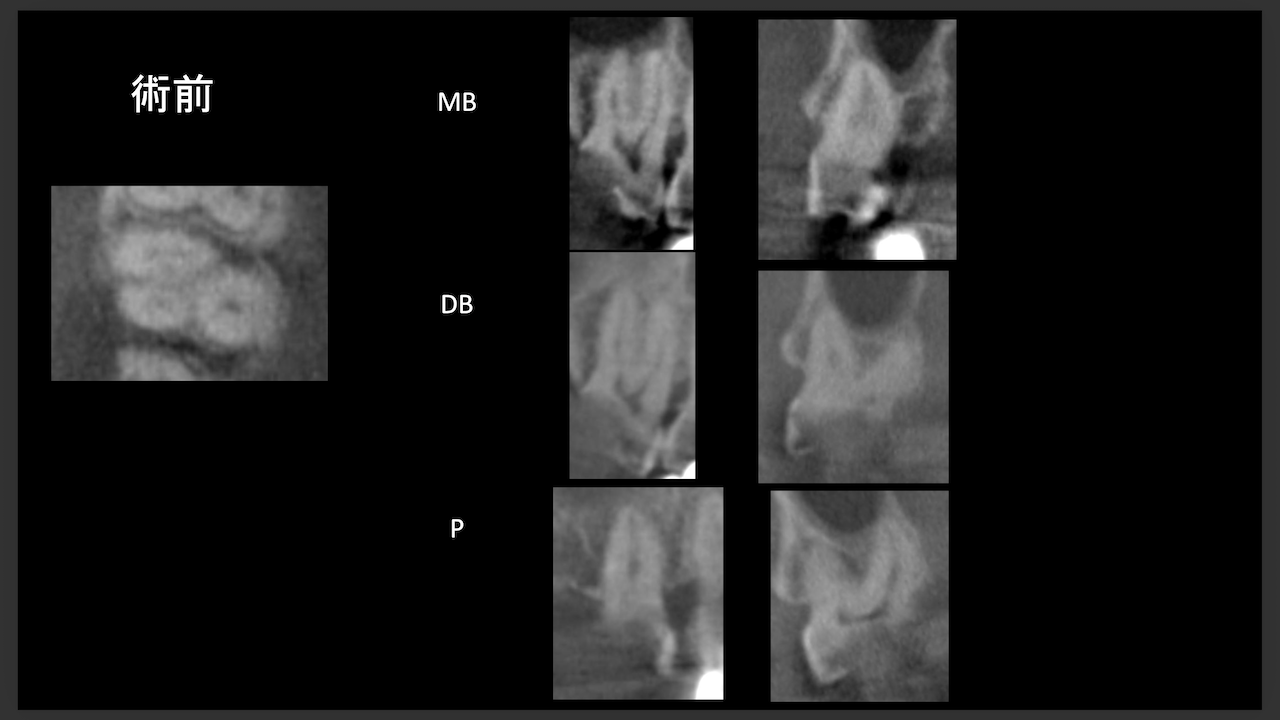

術前にCBCTを撮影したので、MB2がないということを分かった上で根管治療を行っている。

これがCBCTを歯内療法に用いる最大の利点だろう。

上手い!